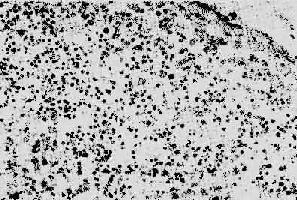

1.淋巴样组织的变化早期及中期,淋巴结肿大。镜下,最初有淋巴滤泡明显增生,生发中心活跃,髓质出现较多浆细胞。随后滤泡的外套层淋巴细胞减少或消失,小血管增生,并有纤维蛋白样物质或玻璃样物质沉积,生发中心被零落分割。副皮质区的淋巴细胞(CD4+细胞)进行性减少,代之以浆细胞浸润。晚期的淋巴结病变,往往尸检时才能看到,呈现一片荒芜,淋巴细胞,包括T、B细胞几乎均消失殆尽,无淋巴滤泡及副皮质区之分,仅有一些巨噬细胞和浆细胞残留(图4-15)。有时特殊染色可显现大量分枝杆菌、真菌等病原微生物,却很少见到肉芽肿形成等细胞免疫反应性病变。

图4-15 AIDS淋巴结

淋巴细胞明显减少,无淋巴滤泡及副皮质区之分